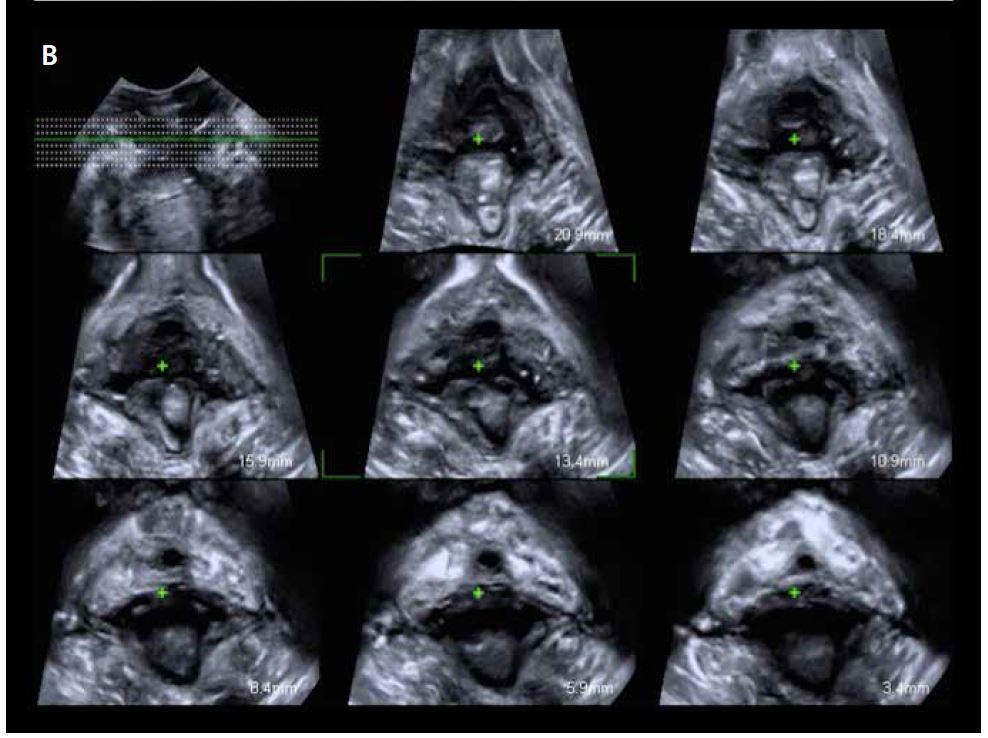

Для оцінки анального сфінктера датчик слід розташувати поперечно над промежиною, нахиливши зонд до анального отвору (мал. 13). Бажано фіксувати об’єм під час скорочення, щоб краще розрізняти тканини. Мультипланарна оцінка дозволяє проаналізувати весь анально-сфінктерному комплекс, розташувавши першу площину на пуборектальному м’язі, а останню – на анальному краю (всього 8 площин) (мал. 14). Відстань між площинами залежить від довжини анального каналу і дозволяє дослідити безперервність сфінктерного комплексу (червона стрілка на мал. 15), а також його товщину, переривчастість, локалізацію дефекту та зміни слизової оболонки анального отвору.

Малюнок 14. Багатоплощинне дослідження для аналізу анально-сфінктерного комплексу.